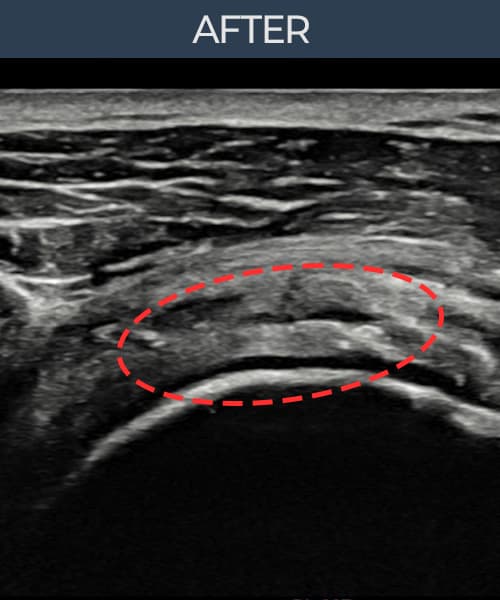

超声确认旋转肌腱袖 关节面侧部分撕裂(8mm × 5mm (肌腱厚度约45%缺损))。缩小缝合术后肌腱连续性恢复,患者回归正常生活。

术后

术前超声确认旋转肌腱袖 关节面侧部分撕裂,冈上肌腱回声不连续伴肌腱缺损(8mm × 5mm (肌腱厚度约45%缺损))。术后超声显示撕裂部位充满再生组织,肌腱连续性恢复,回声模式正常化。

该患者持续肩痛。详细超声检查确认旋转肌腱袖 关节面侧部分撕裂(缺损:8mm × 5mm (肌腱厚度约45%缺损))。在超声引导下实施非手术缩小缝合术。术后佩戴支具约4-6周,随后进行分阶段康复锻炼。随访超声确认肌腱连续性恢复、结构稳定,患者顺利回归日常生活。